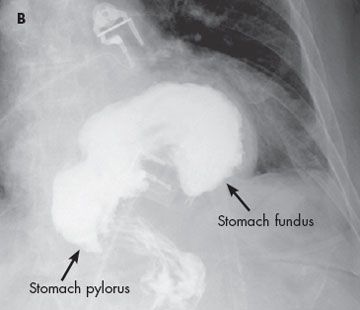

Physical findings were unremarkable. Radiographs of the chest and abdomen showed a gastric bubble in the left lower thoracic cavity (A). A barium swallow showed the stomach within the thorax (B).

An organoaxial volvulus is a type of gastric volvulus-a rare but serious disorder-in which the stomach rotates superiorly along its long axis. The rotation must be 180 degrees or greater and is usually associated with diaphragmatic defects. The rotation causes the greater curvature of the stomach to be superior to the lesser curvature; as a result, the stomach appears upside down. About 60% of cases are organoaxial and 30% are mesenteroaxial, in which the stomach rotates along its short axis. This less common form is usually associated with ligamentous laxity. The remaining 10% of cases are a mixed type.1 The disorder can be further classified as subdiaphragmatic, or primary (33% of cases), in which the cause is usually congenital, or as supradiaphragmatic, or secondary (67% of cases), which is generally caused by trauma or associated with diaphragmatic defects.2